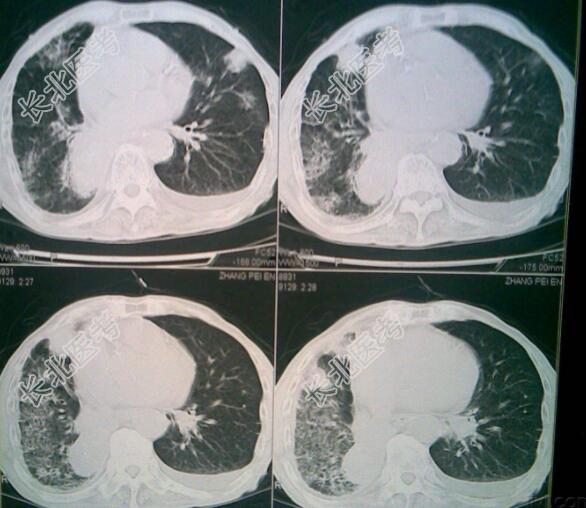

辅助检查:心脏彩超未见异常;血生化基本正常,肺癌指标升高;胸部增强CT:右肺上叶肿块、右肺上叶尖段支气管闭塞、右肺门淋巴结肿大,考虑肺癌伴肺门淋巴结转移;肺穿刺病理:鳞癌;ECT:第三胸椎骨代谢活跃;出院前心电图:正常心电图;胸部CT:右侧气胸,右肺炎症,右上肺点状类软组织密度。